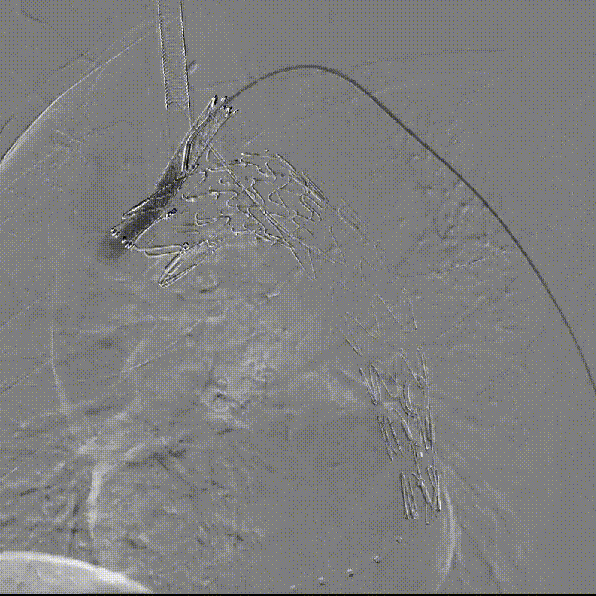

LSA弹簧圈栓塞

造影内漏消失